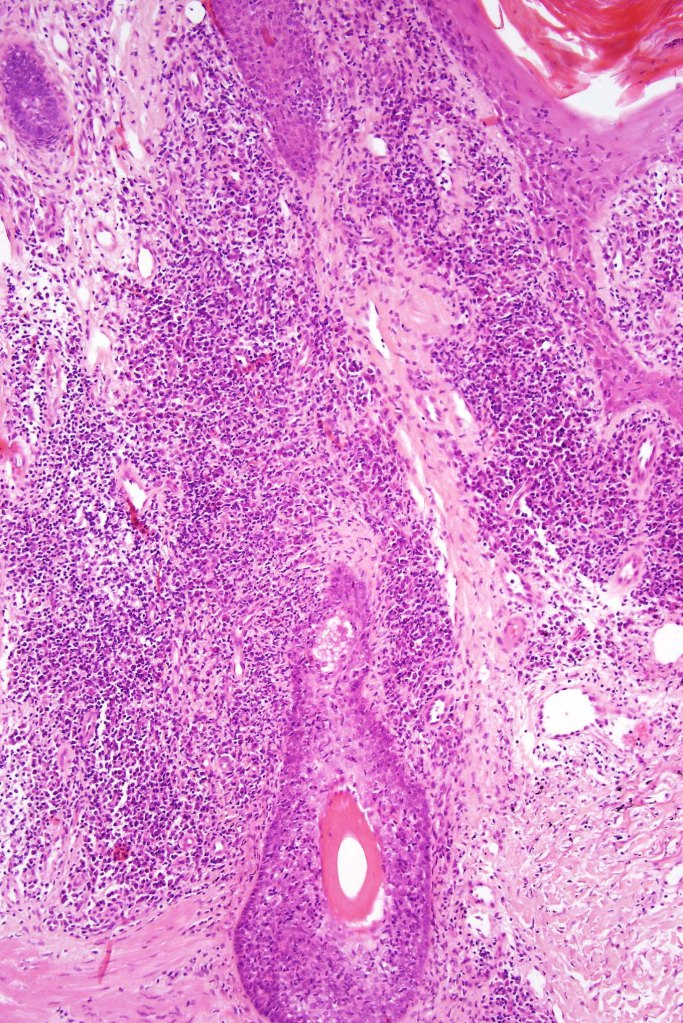

Histological features

•Epidermal involvement often absent

•Follicular infiltration by atypical lymphocytes & Sézary cells

•+/- mucinosis

•+/- syringotropic lesions

•+/- basaloid follicular hyperplasia

•Eosinophils sometimes conspicuous (eosinophilic folliculitis-like appearance)

•Granulomatous inflammation secondary to follicular destruction

•Large cell transformation occasionally present